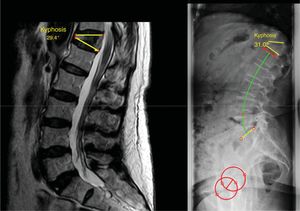

In patients who present with a rigid angular kyphosis (1 B), if compensated, treatment could be conservative. This scenario is rare and usually occurs in the thoracic area.7 If it is located in the thoracolumbar hinge or at the lumbar level, surgery may be necessary (Fig. 6). Multiple surgical options have been described. There is the traditional open posterior approach with a pedicle subtraction osteotomy initially described by Heinig in 1985 with the ‘eggshell’ or decancellation technique,18 with the inherent risk of bleeding and neurological complications with the classic technique. The combined anterior and posterior approach has also been described to perform an anterior arthrodesis by corpectomy and placement of an intersomatic cage combined with a posterior approach.12 The advantages of this approach are direct decompression of the vertebral body fragments compressing the canal and solid reconstruction of the anterior spine. Good results have been published with this technique, but due to the osteoporotic nature of the fracture, and the frailty of the patient, combined approach surgery may prolong surgical time and increase the risk of bleeding and complications related to an anterior approach (lumbar, thoracolumbar, or thoracic). Implant subsidence in osteoporotic bone has also been reported. Suk et al. compared both approaches,19 and concluded that the posterior approach offers advantages over the combined approach, such as better correction of kyphosis and less surgical time and bleeding. Finally, recent studies have published promising results with a simplified decancellation osteotomy technique combined with minimally invasive instrumentation.20–22 This technique minimises bleeding and neurological complications, and improves postoperative pain control and functional recovery. In these cases where the patient is compensated, short posterior instrumentation (with two levels below the osteotomy and two to three levels above the osteotomy) can be performed with good results.

Illustration of a case with a stage 1 B C, showing that it compensates with a lumbar hyperlordosis mechanism (note a lumbar lordosis of 74° for a pelvic incidence of 54°). The patient was treated with a decancellation osteotomy and short instrumentation and normalisation of the lumbar hyperlordosis is observed on the 5-year postoperative control X-ray.